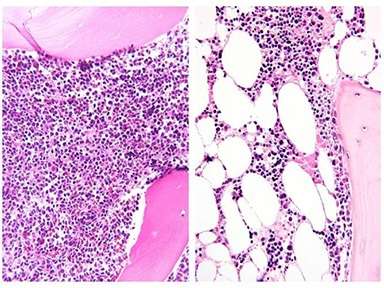

Bone Marrow Before and After Chemo

Bone marrow before and after induction chemotherapy: Bone marrow biopsy from an adolescent patient at diagnosis of ALL (left) and after one month of chemotherapy (right). Marrow is full of ALL cells at diagnosis, but these are largely replaced by large adipocytes (white ovals)